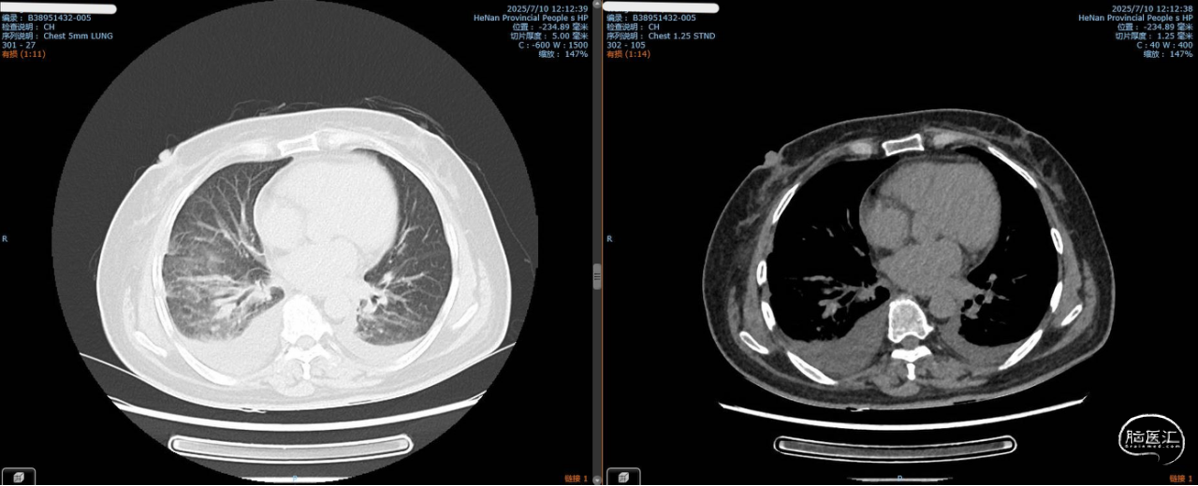

术后第四天,胸部CT提示重度肺炎。

2025-7患者再次入院拟手术治疗,术前查体右侧肢体肌力4级,2025-7-7完成EDAS手术,术后第三天患者出现咳嗽咳痰、发热,次日患者病情进展,精神差、进食差、频繁呕吐和腹泻,结合头胸部CT及实验室检查明确患者双肺重度肺炎、肺水肿、胸腔积液、心衰、酮症酸中毒;予以转入CCU专科治疗,治疗期间患者出现口角歪斜、言语不清、右侧肢体肌力降低至4-级,头部MRI提示左侧额顶叶急性脑梗死;术后第七天内环境及心肺功能稳定后转回普通病房;术后第十天患者肌力和言语不清开始改善,至术后第十四天出院患者口角歪斜、言语不清明显改善,右侧肢体肌力改善至5-级。